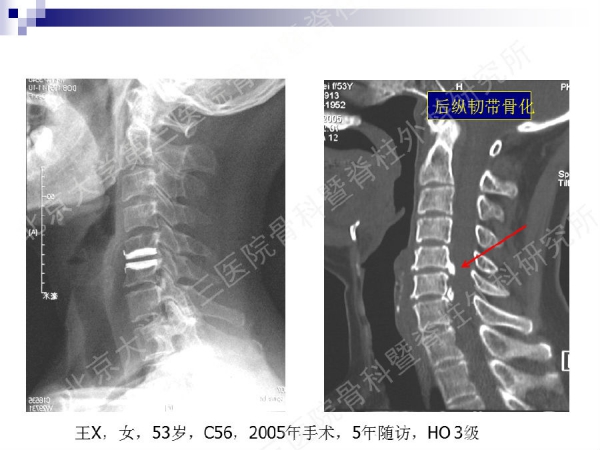

今天,在北京大学第三医院骨科暨脊柱外科研究所刘忠军教授分享的《颈椎人工椎间盘置换手术注意问题》课件中,他将通过大量影像资料、临床研究数据和长期随访结果,给大家介绍现阶段最重要的颈椎非融合技术——人工椎间盘置换术的适应证、禁忌证和其他需要密切注意的一些问题,提醒同道关注与手术技术及内植物相关的尺寸、终板顺列、中心轴线顺列等问题,严格把控手术指征,规范、精准地开展颈椎人工椎间盘置换手术,保障手术疗效。